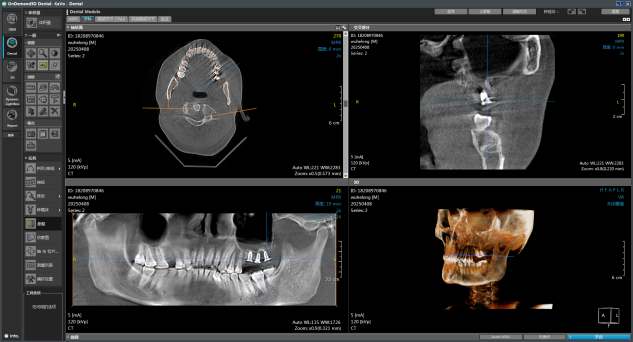

面对武先生到院拍的 CT 影像,杨彦春主任团队启动「复杂病例三阶评估机制」:

1. 立体影像研判:通过锥形束 CT 三维重建,精准定位两块游离骨片位置

4. 借助数字化导板实现 26/27/28 牙位精准种植